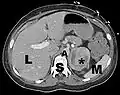

Das * markiert das Phäochromozytom.

Wenn die Bestimmung der Plasma-Metanephrine wiederholt ein positives Ergebnis bringt, muss eine weiterführende Lokalisationsdiagnostik durchgeführt werden. Dies geschieht mittels bildgebender Verfahren wie Computertomographie und Sonographie oder MRT-Bildgebung. Bei der CT ist zu berücksichtigen, dass beim Einlaufen von Jod-Kontrastmittel Katecholamine ausgeschüttet werden können, was bei der MRT nicht der Fall ist. Die nuklearmedizinische Methode der MIBG-Szintigrafie (Metaiodobenzylguanidin) dient vor allem dem Ausschluss von Phäochromozytomen außerhalb der Nebenniere. Diese Substanz lagert sich vornehmlich in den betroffenen chromaffinen Zellen des Phäochromozytoms ab. Die neueste und zuverlässigste Form der nuklearmedizinischen Methode ist bei Phäochromzytomen das so genannte DOPA-PET. Es wird zurzeit (Stand 2012) in Deutschland allerdings lediglich in wenigen Zentren angeboten. Zusätzlich muss auf alle Fälle nach Tumoren eines eventuellen MEN-Syndroms gesucht werden.